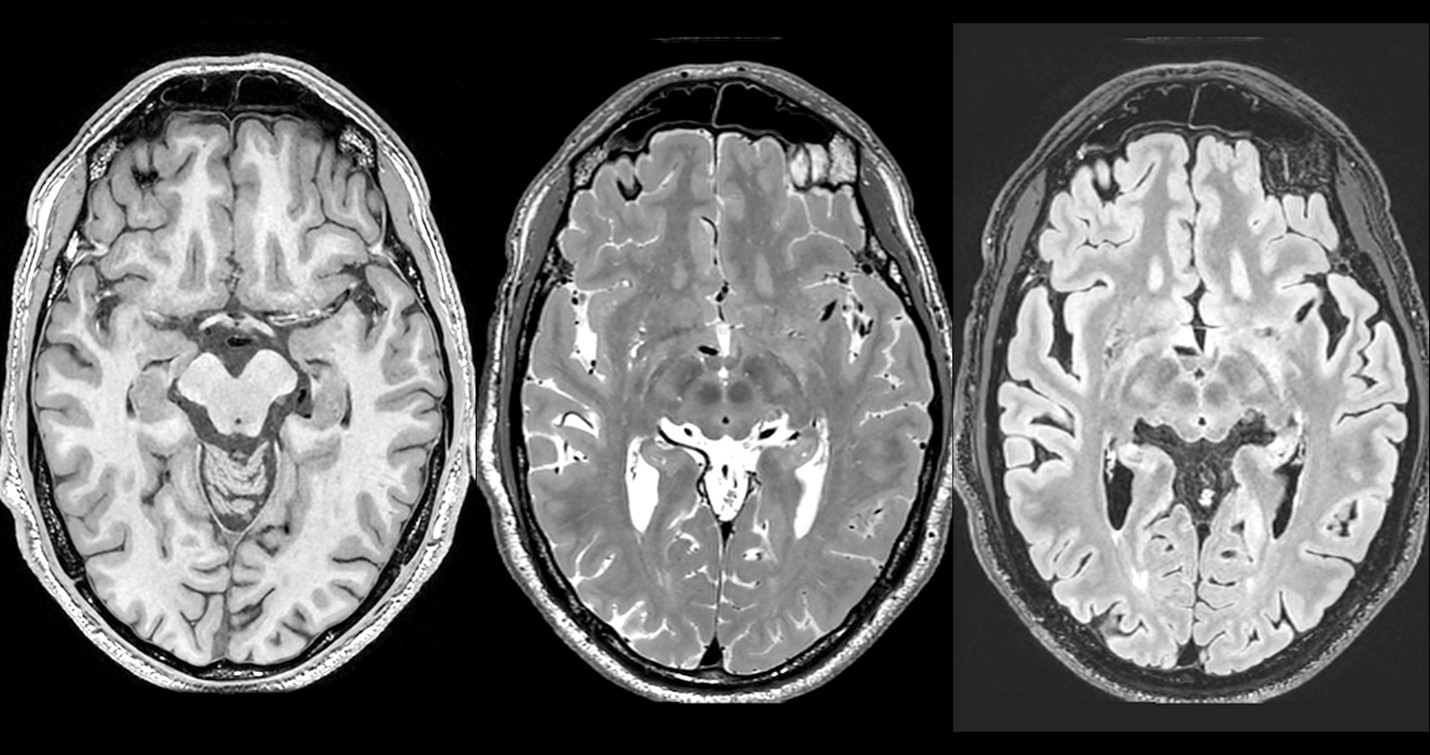

A research volunteer’s brain scan on the MAGNUS shows high-resolution images (0.7mm in all three axes) using three different protocols that are designed to reveal different aspects of brain structure.